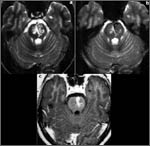

Un RMN cerebral a indicat un infarct pontin, predominant pe partea stanga. Zilele ce au urmat pacientul a inceput sa isi revina progresiv.

La o saptamana dupa cele relatate, cand pacientul a fost ridicat la verticala acesta a avut un episod de declin neurologic acut, cu hemipareza tranzitorie si mioclonii aparute ca urmare a hipotensiunii ortostatice. Un nou CT nu a indicat modificari semnificative in dimensiunea infarctului .